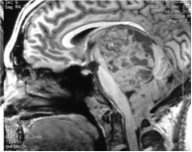

Pre

Post